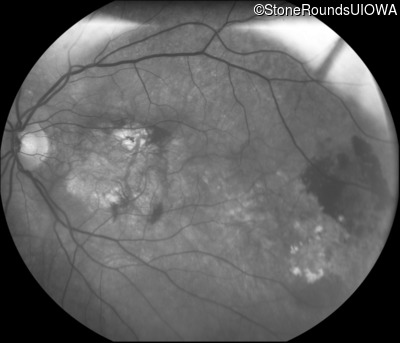

Fundus Photography - Right - 20/200 +2

Exemplar